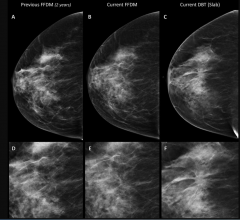

October 25, 2018 — iCAD Inc. announced new clinical research demonstrating positive outcomes supporting the use of the ...